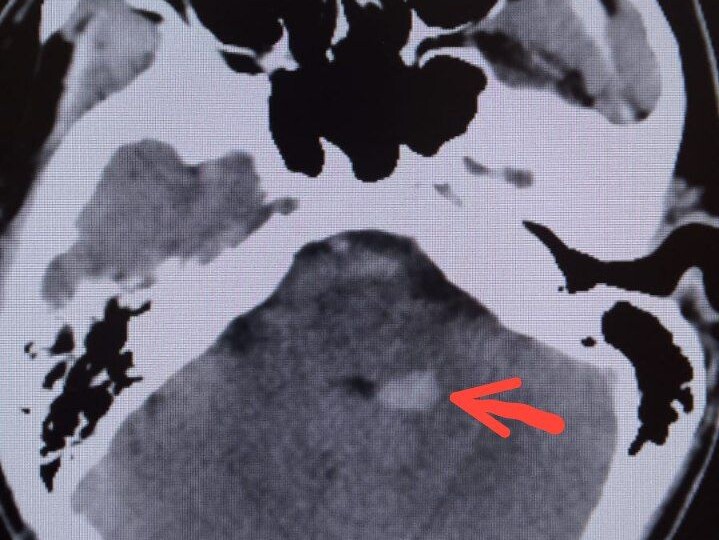

Страх, возникающий при головокружении, заставляет многих идти выполнять МРТ головного мозга, самостоятельно. Вроде как, логично- кружится голова, значит МРТ головного мозга нужно сделать. Но не так все однозначно и случаев, когда ничего "подозрительного" на том самом МРТ не находят в разы больше, когда оно выполняется обоснованно. Потому томография (компьютерная и магнитно-резонансная)- это методы которые я не рекомендую выполнять до приема врача по поводу головокружения или шаткости при ходьбе. Вот почему: Кстати, это же относится и к УЗИ сосудов шеи и головного мозга. В подавляющем большинстве случаев самостоятельного проведения- необоснованно и бесполезно, как исследование для выявления причины головокружения. Что я поддерживаю в качестве первичного (базового) обследования, при первичном обращении: Этого достаточно. Остальное- после осмотра. Зачастую вообще ничего не назначается (ни МРТ, ни дуплексное сканирование) для уточнения причины и ее решения Не спешите выполнять обслед

Шатает в стороны, нарушилась координация движений, плывет картинка перед глазами- иногда не так просто собрать пазл точного диагноза при таких жалобах В феврале у меня были трое пациентов 50+, у которых это все было + у кого то были иные жалобы, но течение их заболевания не было похоже на выше описанное ПППГ и причина была другая- дегенеративное заболевание головного мозга. Это группа заболеваний с прогрессирующим течением, построенным нарастанием симптомов На самом деле, эта тройка симптомов - повод , чтобы врачу в поиске диагноза следовать "от общего к частному" и такие ощущения вполне могут быть проявлениями анемии, сердечно- сосудистых заболеваний. Слишком они не специфичны Но есть отдельная группа неврологических заболеваний - дегенеративные заболевания нервной системы. Начало может быть с такими симптомами, но с особенностями, иногда, яркими, а иногда менее заметными ✅ Прогрессирующее течение- за год- два симптомы нарастают ✅ Шаткость сопровождается падениями, которые могут